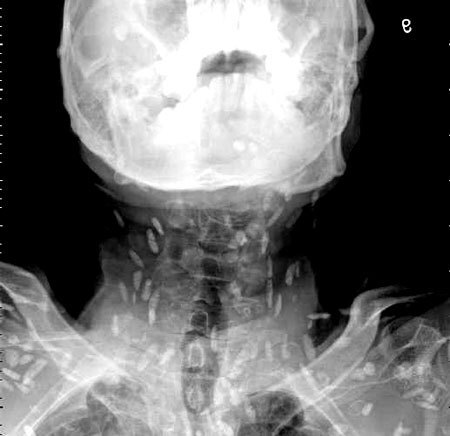

이 기생충들이 뇌조직으로 침투할 경우 생명에 위험을 초래할 수 있습니다. 회를 섭취한 남성의 사례에서도 복부통증과 피부가려움 등의 증상이 나타나, 엑스레이 결과 전신에 기생충이 퍼져 있는 것이 확인되었습니다. 따라서, 이러한 기생충에 감염될 경우 조기에 발견하고 치료하는 것이 매우 중요합니다.

마지막으로, 위에서 언급한 엑스레이 사진과 관련된 환자의 경우, 의료진은 해당 환자가 특별한 치료를 받지 않았다고 밝혔습니다. 만약 머리, 척수, 눈에 이상이 없다면 치료를 받을 필요가 없다고 말하고 있습니다. 또한, 사진 속의 유충들은 석회화되어 생존할 수 없는 상태이므로 특별한 조치가 필요하지 않다고 설명되었습니다. 그러나 해당 환자의 뇌에 낭종이 있는지 확인하기 위해 MRI 검사를 기다리고 있다고 전했습니다.